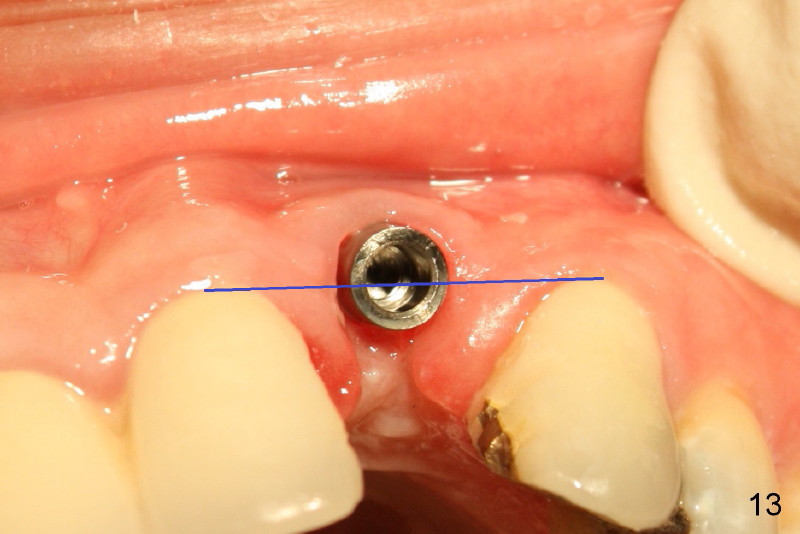

Segmental Osteotomy for Misplaced Implant

This corrective surgery was performed by Dr. Bernee Dunson.

Xin Wei, DDS, PhD, MS 1st edition 12/21/2011, last revision 12/23/2011